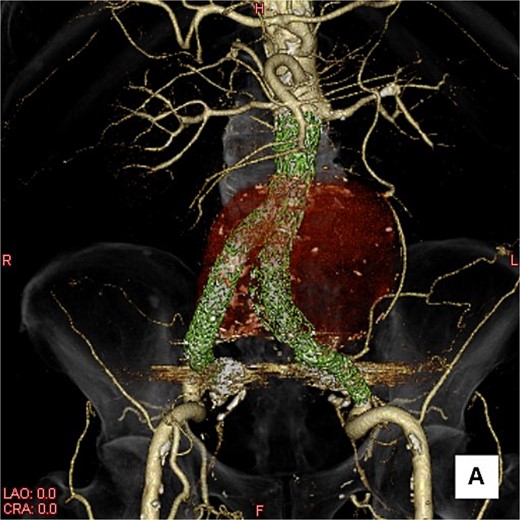

A three-dimensional image. The AAA is shown in transparent red, and the framework of the stent grafts is displayed in green. The landing zones and overlaps of the stent grafts were satisfactory.

This time, he was brought to the emergency department with a chief complaint of abdominal pain. His medical history includes Stage 4–5 chronic kidney disease (CKD), with an estimated glomerular filtration rate (eGFR) of approximately 15 mL/min/1.73 m2, secondary to nephrosclerosis and diabetic nephropathy, as well as persistent atrial fibrillation, which was treated with warfarin. Upon admission, laboratory results revealed a hemoglobin level of 6.2 g/dl and a prothrombin time—international normalized ratio (PT-INR) of 6.05. Contrast-enhanced CT demonstrated an AAA measuring 118 × 107 mm, enlarged from 98 × 94 mm 2 months prior, and left retroperitoneal hematoma. IMA and one pair of lumbar arteries were enhanced only in the delayed phase, but blood flow into the aneurysm was not clearly observed (Fig. 1). Given that the landing zones and overlaps of the stent grafts were satisfactory (Fig. 2) and that no type I or type III endoleaks were identified, a ruptured AAA due to TIIEL from the lumbar artery or IMA was highly suspected. We administered 3000 IU/kg of lyophilized human prothrombin complex concentrate in response to the significant prolongation of PT-INR and proceeded with open surgery for ligation of the feeding artery and aneurysmorrhaphy. Intraoperatively, no pulsation was found on the aneurysm. Incision of the aneurysm revealed a large amount of thrombus, which was removed, and then pulsatile bleeding was identified from a lumbar artery (Fig. 3), the ostium of which was sutured from within the aneurysm. This was consistent with the left lumbar artery of the pair enhanced on the preoperative CT and was suspected to be responsible for the rupture. Oozing was also noted from several other lumbar arteries, which were similarly sutured closed. No leak was observed from the proximal or distal ends, nor from the junctions of the stent grafts, and no damage to the stent grafts was observed (Fig. 4). Following this, aneurysmorrhaphy was performed, and the abdomen was closed. The postoperative course was uneventful. A plain CT on postoperative day (POD) 14 showed a reduction in the aneurysm size with no apparent leaks (Fig. 5). The patient was discharged home on POD 24. Although the preoperative eGFR was 8.8 ml/min/1.73 m2, no postoperative deterioration was observed. It gradually improved back to baseline, and dialysis was not required during the follow-up period.